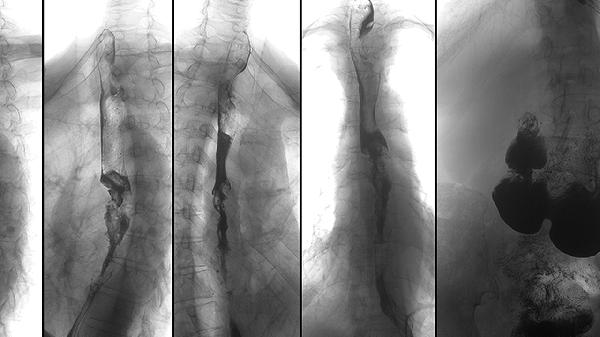

2、脊柱侧弯

脊柱侧弯是退变性脊柱侧畸形的典型表现,脊柱向一侧弯曲,可能伴有椎体旋转。侧弯角度通常较小,但随着病情进展可能逐渐加重。脊柱侧弯可能与骨质疏松、椎间盘退变、肌肉萎缩等因素有关。患者可通过佩戴支具、进行脊柱稳定性训练等方式改善侧弯,严重者可能需要手术治疗。